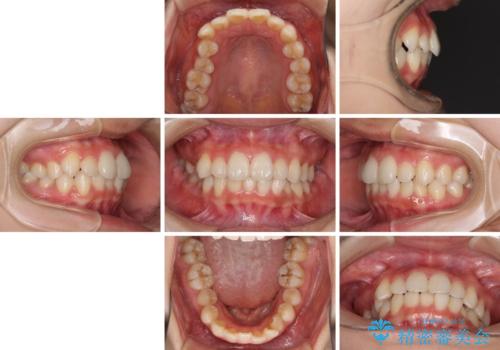

- 前歯のデコボコを気にして来院された患者様です。

叢生と捻転が随所に認められるものの、マウスピースで十分対応可能であったため、インビザラインにて矯正治療を行うこととしました。

マウスピース矯正は毎日しっかりと装着することがとても大切です。

こちらの方はしっかりと指示を守って装着してくださったため、予定通り治療を終えることができました。